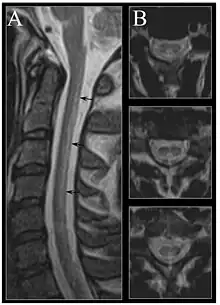

| Image of the cervical spinal cord in vitamin B12 deficiency showing subacute combined degeneration. (A) The midsagittal T2 weighted image shows linear hyperintensity in the posterior portion of the cervical tract of the spinal cord (black arrows). (B) Axial T2 weighted images reveal the selective involvement of the posterior columns. | |

Severe vitamin B12 deficiency is associated with subacute combined degeneration of the spinal cord, which involves demyelination of the posterior and lateral columns of the spinal cord.[103] Symptoms include memory and cognitive impairment, sensory loss, motor disturbances, personality changes, disorientation, irritability, dementia, loss of posterior column functions and disturbances in proprioception.[104][105][106] In advanced stages of vitamin B12 deficiency, cases of psychosis, paranoia and severe depression have been observed, which may lead to permanent disability if left untreated.[103][104][105] Studies have shown the rapid reversal of the neurological symptoms of vitamin B12 deficiency, after treatment with high-dose of vitamin B12 supplementation; suggesting the importance of prompt treatment in reversing neurological manifestations.[107]

MRI of the brain may show periventricular white matter abnormalities. MRI of the spinal cord may show linear hyperintensity in the posterior portion of the cervical tract of the spinal cord, with selective involvement of the posterior columns.